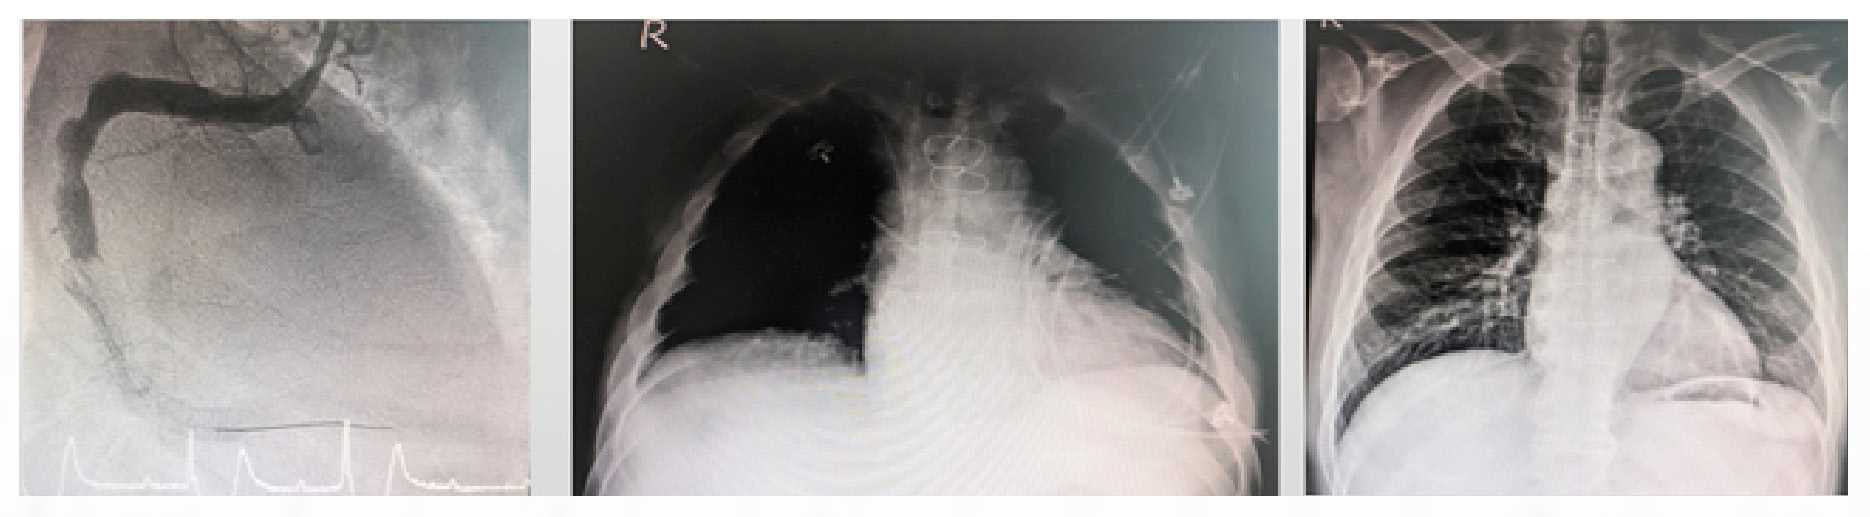

楊翔宇主任分享,一名 42歲男性患者因急性心肌梗塞送醫,心導管檢查發現冠狀動脈嚴重阻塞,在接受支架置放過程中突然心跳停止。醫療團隊立即施行葉克膜輔助心肺復甦,但患者仍出現嚴重心因性休克與急性肺水腫。

醫療團隊隨即植入 雙心室短效型心室輔助器 CentriMag,成功穩定患者生命徵象。後續治療中,患者先轉換為長效型心室輔助器,最終順利接受心臟移植並康復出院。

另一名 53歲男性患者因急性心肌梗塞導致右心室衰竭,即使接受心導管治療與冠狀動脈繞道手術仍無法恢復心臟功能。醫療團隊植入右心室短效型心室輔助器 CentriMag 支援循環,成功維持患者生命並等待心臟移植,最終也順利完成移植並康復出院。